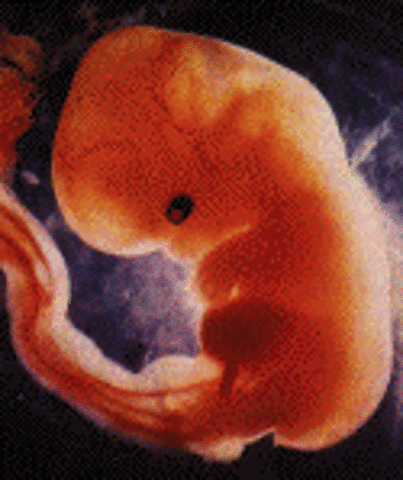

• week 6

week 6

Embryo is about 8 mm in length. Spinal cord begining to close.

• week 7

week 7

One chamber of the heart is beating.arms and legs beging to form.